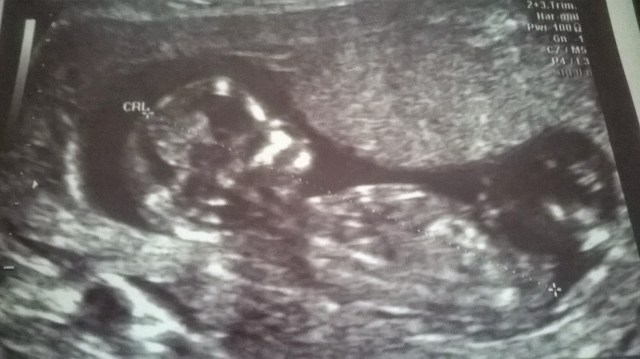

Pelko oli turhaa, pikkuinen oli heti käsi ojossa vilkuttelemassa ja oli varmaankin unille rupeamassa. 🙂 Niin pieni ja hauras. Kätilö oli todella mukava, näytti meille profiilit ja edestä päin kasvot, varpaat ja sormet.

| 12+6 ❤ Kännykkälaatu.. |